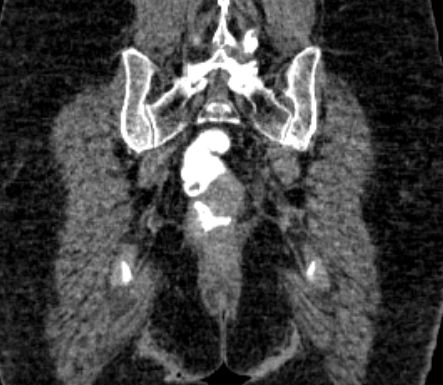

| CT | 66jähriger Mann, dass er seit einigen Wochen Blut im Stuhl gehabt habe.

Eine Koloskopie vor 6 Wochen habe einen unauffälligen Befund ergeben.

Bei der Austastung findet sich ein 5 cm großer schüsselförmiger Krater mit wulstigen Rändern.![]() | ||

Zusätzlich ein 2,5 cm großen Lymphknoten in der rechten Leiste medial der Vena femoralis. ![]() |